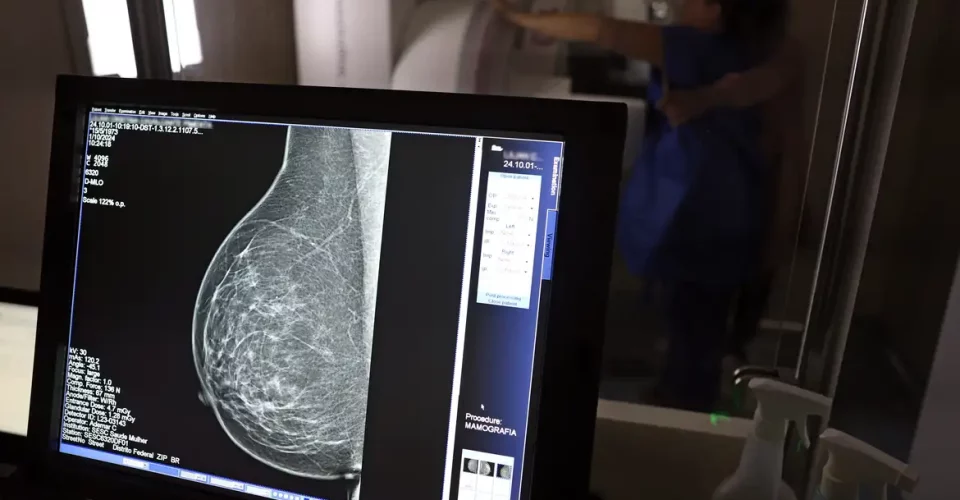

O Ministério da Saúde passou a recomendar o acesso a mamografia, via Sistema Único de Saúde (SUS), para mulheres de 40 a 49 anos – mesmo que não haja sinais ou sintomas de câncer de mama. De acordo com a pasta, a faixa etária concentra 23% dos casos da doença, e a detecção precoce aumenta as chances de cura.

Até então, a orientação era que o exame fosse feito a partir dos 50 anos.

A medida faz parte de um conjunto de ações anunciadas nesta terça-feira (23) voltado para a melhoria do diagnóstico e da assistência. A recomendação para mulheres a partir dos 40 anos é que o exame seja feito sob demanda, em decisão conjunta com o profissional de saúde.

As mamografias via SUS em pacientes com menos de 50 anos, de acordo com a pasta, representam 30% do total, o equivalente a mais de 1 milhão apenas no ano de 2024.